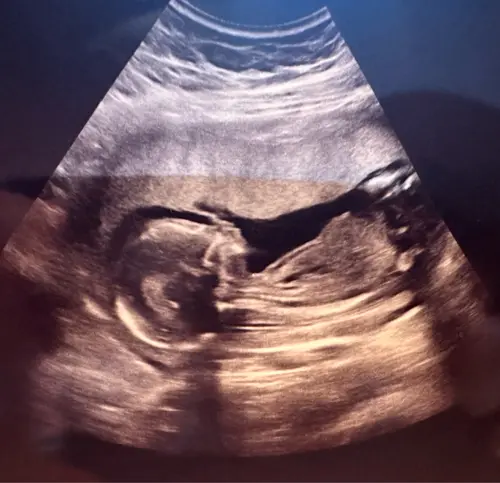

Mädchen oder Junge? 16+4

Huhu! Ich kann leider nichts sehen , weil der Pöpes nicht im Fokus liegt bzw man nicht zwischen die beide schauen kann

Ein jungen 😄